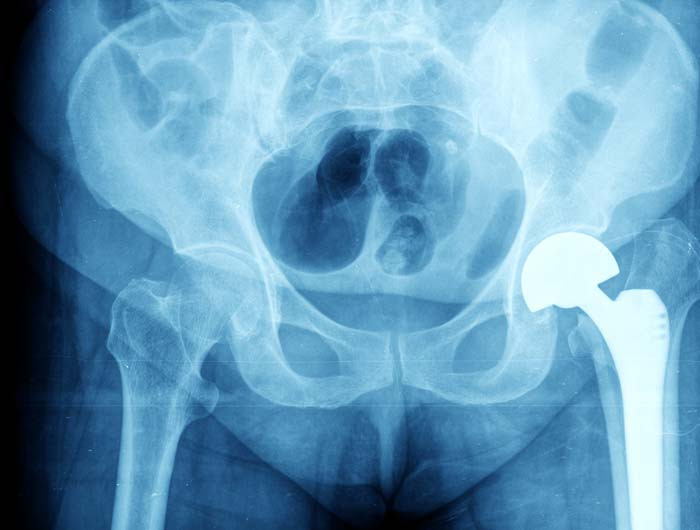

Hip Replacements

Hip replacement is a very effective way of removing the pain from an arthritic joint for the long term. The type of hip replacement that you receive depends on your age and level of function, as wel..